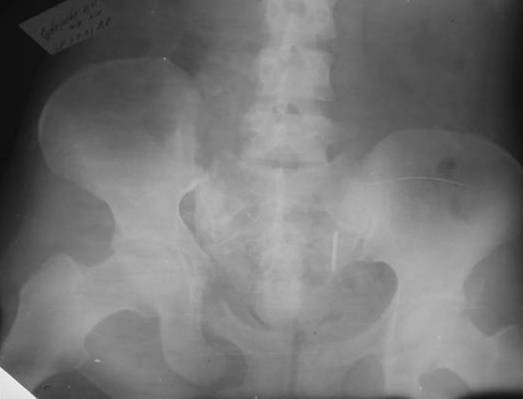

Пациентка С.26 лет. Травма за 6 месяцев до поступления

Укорочение правой нижней конечности до 10см

и 8месяцев после операции